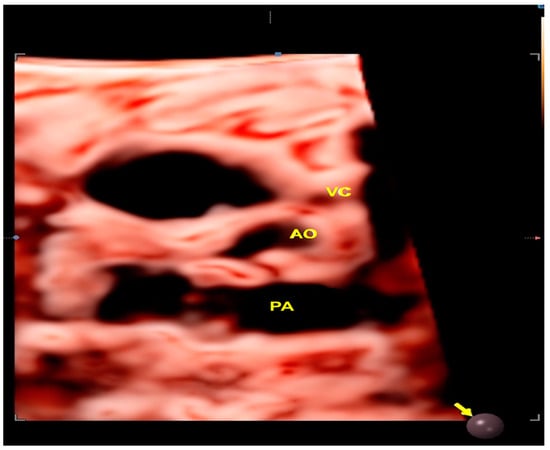

2.1. Anomalous Venous Return

- Malho, A.S.; Bravo-Valenzuela, N.J.; Ximenes, R.; Peixoto, A.B.; Araujo Júnior, E. Antenatal diagnosis of congenital heart disease by 3D ultrasonography using spatiotemporal image correlation with HDlive Flow and HDlive Flow silhouette rendering modes. Ultrasonography 2022, 41, 578–596. [Google Scholar] [CrossRef]

- Tie, H.X.; Ma, B.; Zhang, D.C.; Li, T.G. Prenatal diagnosis of fetal inferior vena cava malformation using HDlive flow combined with spatiotemporal image correlation. Echocardiography 2022, 39, 685–690. [Google Scholar] [CrossRef]

- Li, T.G.; Ma, B.; Gao, Y.H.; Zhang, R.H.; Li, P.L.; Da, Z.Q. Prenatal diagnosis of total anomalous pulmonary venous connection using 2D and HDlive flow combined with spatiotemporal image correlation. Echocardiography 2022, 39, 1269–1275. [Google Scholar] [CrossRef]